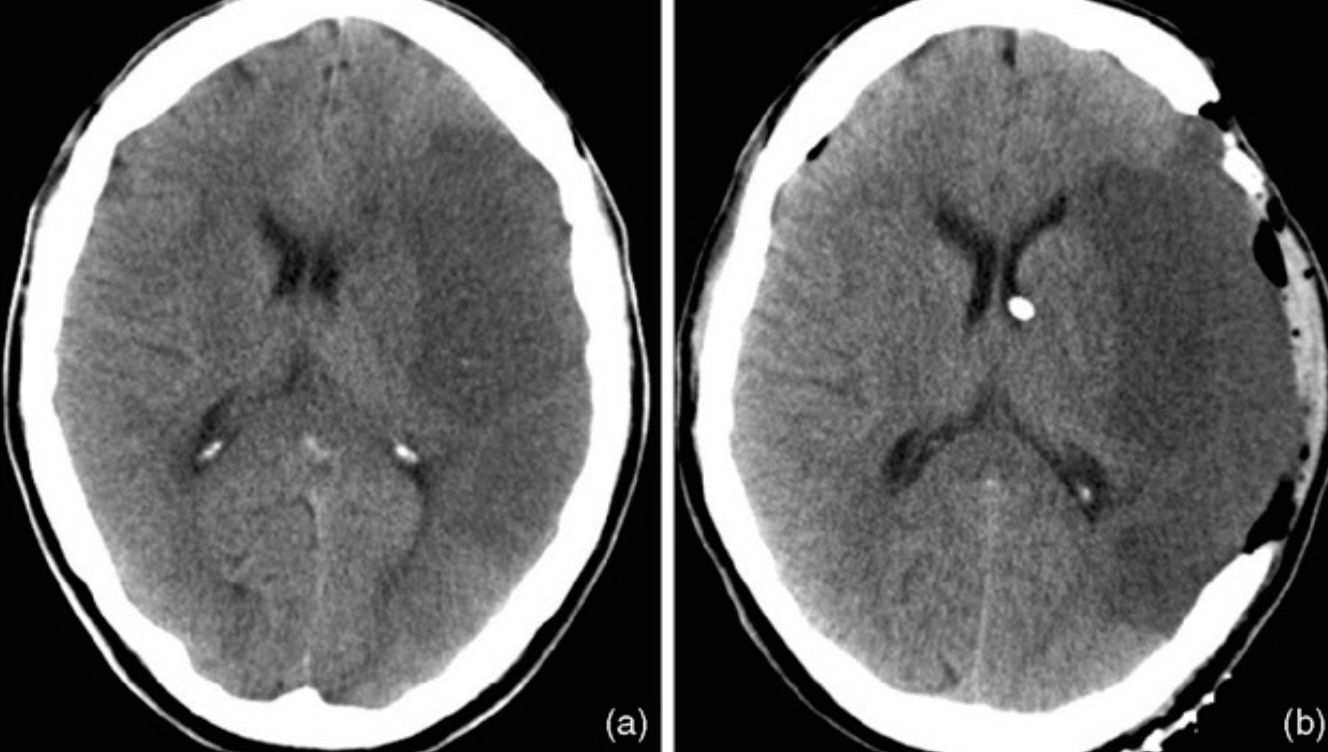

Case 11

-

Describe 2 abnormal findings of the CT?

a. Left hypodense area occupy the left hemisphere (infarction)

b. Left carinotomy mark -

Name vascular territory involved?

a. Middle cerebral artery

Case 12

A 54-year-old woman presented with a sudden onset thunderclap headache and neck pain for 2 days.

A 54-year-old woman presented with a sudden onset thunderclap headache and neck pain for 2 days.

O/E

- Temperature 37°C.

- PR 106 beats/min

- BP 175/106 mm Hg.

- GCS score 14/15

- Pupils- 3 mm diameter, with a light reflex.

- Neck stiffness was ++

-

What is the abnormality in the image shown?

a. Blood mixed with CSF filling the subarachnoid space -

What is the likely diagnosis?

a. Subarachnoid hemorrhage -

What is the abnormality in the image shown?

b. Hyper dinse lesion -

What is the likely diagnosis?

a. Meningitis